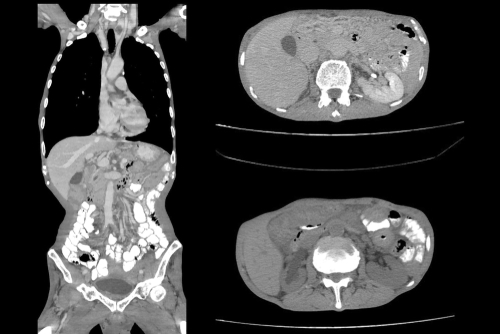

顯影劑(Contrast Media 或 Contrast Agents),又常被稱為造影劑,是一種在進行醫學影像檢查時引入體內的特殊物質。它的主要用途是改變人體內部特定器官、血管或組織的對比度,使這些部位在 X 光、電腦斷層掃描(CT)或磁力共振掃描(MRI)的影像中顯得更為突出和清晰。透過注射或口服顯影劑,醫生能夠更準確地觀察器官的結構及血流情況,從而精準辨識微小腫瘤、血管阻塞、發炎或組織異常。

坊間常有一個迷思,認為所有高階醫學影像檢查都必須使用顯影劑。事實上,並非所有CT或MRI都必須打顯影劑。許多基礎的檢查(例如骨骼結構掃描、部分關節損傷檢查、或是初步的腦部出血篩查)在不注射顯影劑(平掃,Plain Scan)的情況下已經能提供足夠的診斷資訊。是否需要使用顯影劑,完全視乎主診醫生根據患者的具體病歷、疑似疾病的種類以及檢查的目的來作出的專業判斷。